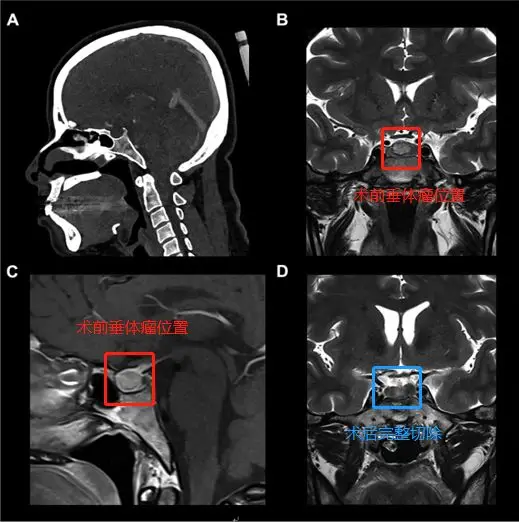

术前(红色区域):A、C图位于蝶鞍中央的9mm垂体微腺瘤。B图表示计算机断层扫描仪显示了蝶窦的鞍周型气管化。

手术过程:使用筷子手法进行广泛的蝶窦切开术,从手术区域清除血液并解剖假包膜平面,进而完整地切除肿瘤(不分块切除,防止肿瘤残留)

术后(蓝色区域):D图显示垂体瘤被肉眼下完整切除,且完成内分泌治疗。